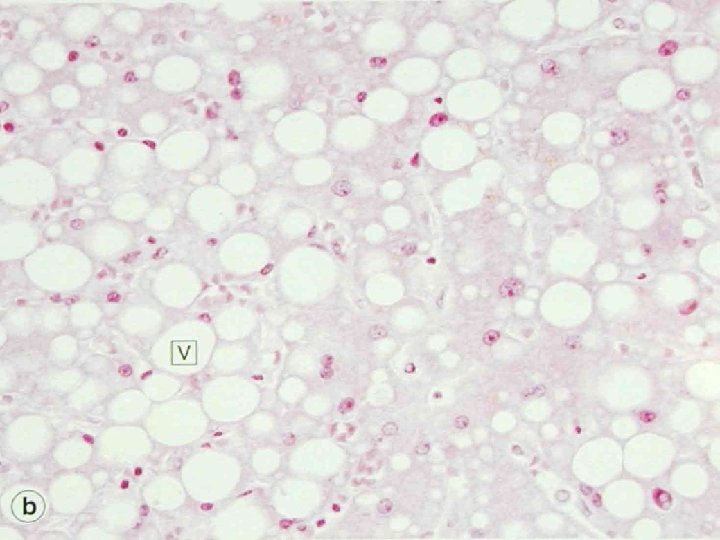

Morphology of Reversible cell injury • Ultrastructural damage to mitochondria – Low-amplitude swelling – )High-amplitude swelling: irreversible( • Swelling of cellular organelles: hydropic degeneration/cloudy swelling • Fatty change: sublethal impairment of metabolism: liver

Fat necrosis • Hard yellow-gray material: fat tissue • Examples: – Retroperitoneal fat necrosis associated with acute of the pancreas – Traumatic fat necosis: breast, buttock